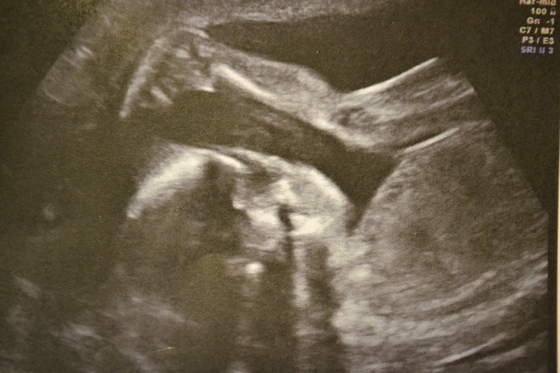

), bo miał niedobrą do tego badania pozycję i uparciuch nie chciał się ruszyć - tylko co jakiś czas mnie kopał. Z resztą zobaczcie same jak młody leży:

Ładnie już dzidzia waży